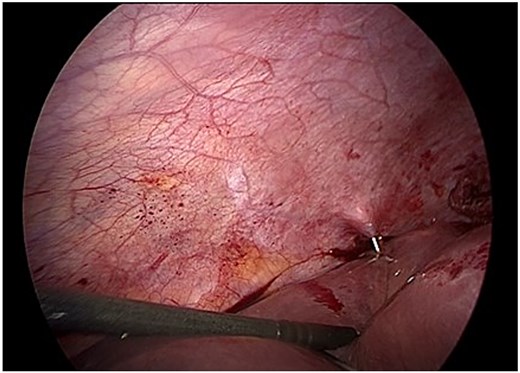

Following aspiration, the germinative membrane was carefully extracted using an endoscopic retrieval bag through a 10 mm trocar. The residual cavity was inspected with a 30° scope to detect any biliary communication (Fig. 3).

Endoscopic removal of the germinative membrane using an endobag through the 10 mm trocar. Inspection of the residual cavity was performed with a 30° laparoscope.